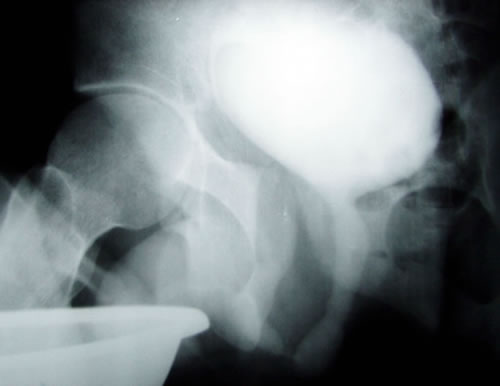

Рентгенография:

2. Микцонная цистография